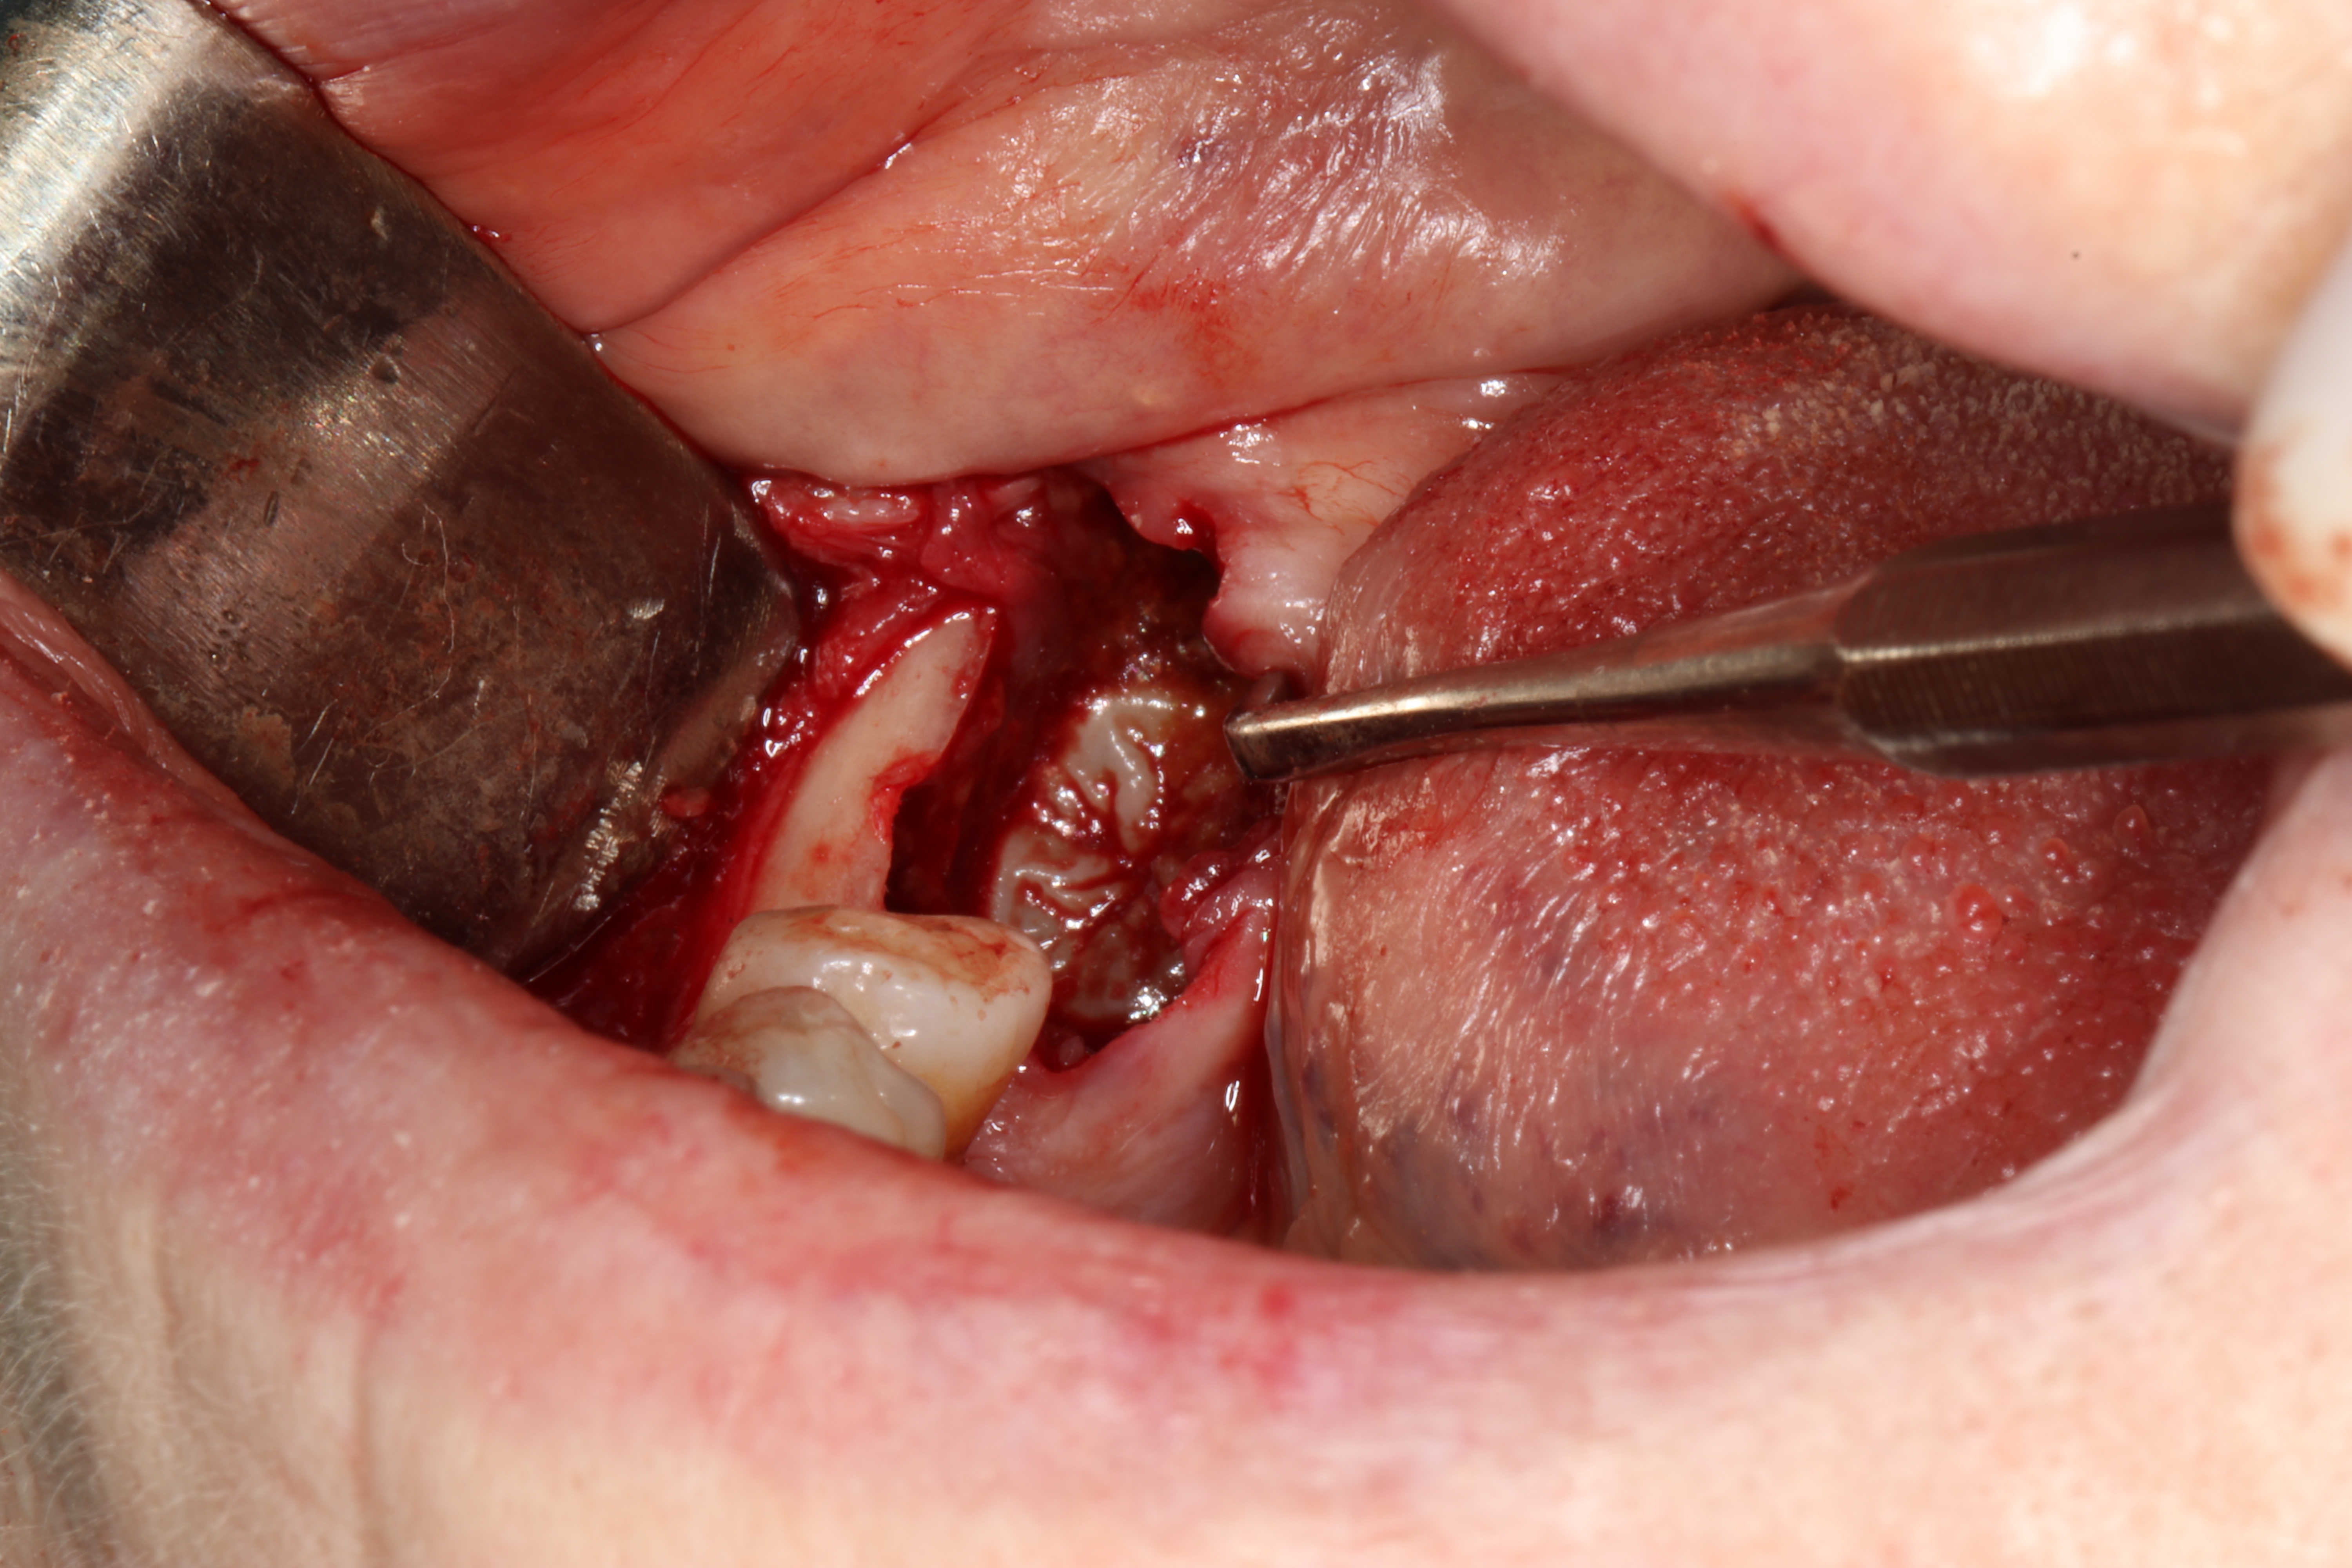

W znieczuleniu nasiękowym i przewodowym z zastosowaniem dentocaine 4% (podano 4 ampułki) usunięto minimalnie inwazyjnie ząb 47. Następnie wykonano płat śluzówkowo-okostnowy i dotarto do jamy torbieli. Usunięto ząb 48 oraz wyłuszczono zmianę, którą następnie oddano do badania histopatologicznego. Ranę zaopatrzono szwami 4-0 oraz opatrunkiem chirurgicznym (ryc. 2).

Ryc. 2. Zdjęcia śródzabiegowe: a) okolica operowana; b) stan po usunięciu zęba 47; c) wykonanie płata śluzówkowo-okostnowego, widoczny ząb 48; d) wyłuszczenie zmiany, obecna gruba torebka łącznotkankowa; e) loża pozabiegowa; f) usunięte zęby 47 i 48; g) stan pozabiegowy; h) aspirat ze zmiany (grudzień 2020).